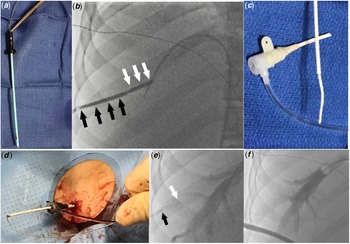

We attempted to perform transbaffle puncture through the left femoral vein; however, we were unable to position the transseptal needle at a safe location. Therefore, the decision was made to proceed with transhepatic access. From the left femoral vein access a 7-Fr wedge catheter (Arrow, Morrisville, NC) was placed in an adequately sized right hepatic vein. Under biplane fluoroscopy guidance a 15 cm 22-gauge Chiba needle (Cook Medical, Bloomington, IN) was advanced toward the wedge catheter. After accessing the hepatic vein, the access wire was exchanged for a 0.035" Amplatzer Super Stiff guidewire (Boston Scientific, Marlborough, MA). Upon advancing the guidewire into the Fontan circuit, the guidewire spontaneously crossed through a small baffle leak into the left atrium. An 8.5-Fr steerable Agilis sheath (St Jude Medical, St Paul, MN) was advanced over the guidewire across the baffle leak. Through the Agilis sheath, the mapping and ablation procedures were successfully completed. To mitigate the risk of bleeding from the transhepatic tract, we decided to close it. The Agilis sheath was pulled back inside the Fontan baffle over a guidewire and was exchanged for a 9-Fr 10 cm Pinnacle sheath (Terumo Medical, Somerset, NJ), and the dilator and wire were removed. The tip of the 9-Fr dilator was cut to match the length of the sheath. A 0.035” short access wire was inserted inside the dilator. The wire was secured within the dilator using a metallic hemostat, keeping the wire tip flush with the cut tip of the dilator (Fig 1a). This modification was created to stiffen the dilator and fill its lumen, so that gelatin “torpedoes” could be pushed with the dilator through the sheath. A 2 x 6 x 0.7 cm Surgifoam (Ferrosan Medical Devices, Soeborg, Denmark) gelatin sponge was chosen. The sponge was compressed by rolling a 5cc syringe over the gelatin sponge which was then cut into strips. The strips were turned into “torpedoes” by tightly rolling them. Two “torpedoes” were loaded inside a cut 5-Fr sheath. The 9-Fr sheath was pulled back inside the transhepatic tract to ensure that the gelatin “torpedoes” could be precisely placed within the parenchymal tract rather than within hepatic vein. An angiogram through the sidearm of the 9-Fr sheath confirmed the location of the sheath tip to be within the hepatic parenchyma (Fig 1b). Two “torpedoes” were loaded inside a cut 5-Fr sheath (Fig 1c) and pushed inside the 9-Fr sheath with the help of the stiff end of the 0.035” access wire (Fig 1d). The cut 5-Fr sheath was removed and the torpedoes were deployed sequentially inside the tract by pushing them with the modified 9-Fr dilator while pulling the sheath back (Fig 1e). An angiogram in the right hepatic vein showed no residual contrast flow inside the hepatic tract (Fig 1f) and no blood was seen at the skin access site. The next day an abdominal ultrasound showed no hemoperitoneum or intrahepatic haematoma.

Figure 1. (a) The dilator of the 9-Fr sheath was cut to match the length of the sheath and the access wire was clipped to the dilator, with the wire end flush with the end of the dilator. (b) Angiogram through the 9-Fr sheath showing the sheath tip is inside the transhepatic tract (black arrows delineate the sheath inside the tract, white arrows delineate the distal transhepatic tract with no sheath inside it). (c). Loading gelatin sponge “torpedoes” inside the cut 5-Fr sheath. (d). Loading gelatin “torpedoes” inside the 9-Fr sheath. (e). Angiogram through the wedge catheter after deploying the first gelatin “torpedo” shows no contrast filling the distal part of the transhepatic tract (white arrow delineates the end of the sheath, black arrow delineates the end of the dilator). (f). Final angiogram in the right hepatic vein after deploying the second torpedo showing no contrast filling the hepatic tract.